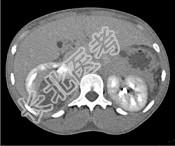

- 单项选择题一女性患者,一月前出现尿频、尿急等症状为引起注意, 现有高热,阅图后最可能的诊断为 ( )

A、急性肾盂肾炎

B、肾脓肿

C、多囊肾

D、肾结核

E、肾癌